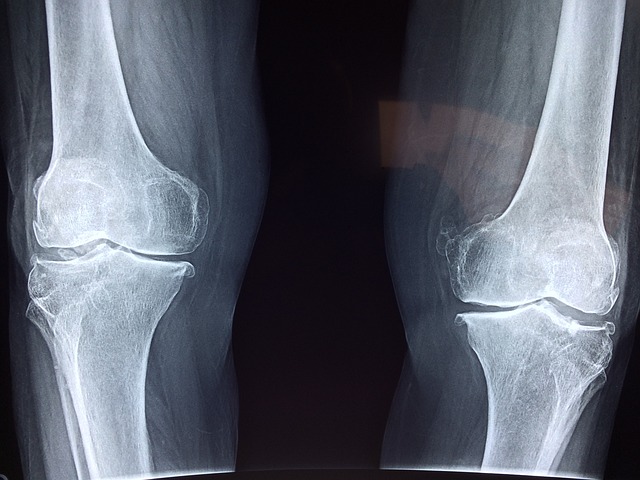

퇴행성 관절염으로 고생하시는 많은 분들이 연골의 구성 요소인 글루코사민과 콘드로이친을 보조제 형태로 섭취하고 계십니다.

무릎이나 손가락 관절염은 치료도 쉽지 않고 나이가 들수록 그 위험도가 증가하는데요. 글루코사민과 콘드로이친 하루 권장량 및 부작용 확인해보시고 구입하세요

글루코사민과 콘드로이친은 연골의 구성 성분이기 때문에 관절의 구조에 영향을 미칠 수 있다는 주장이 제기되었으나, 실제로 글루코사민과 콘드로이친이 관절 구조에 영향을 미치는지는 불확실합니다.

무릎 관절염에 대한 글루코사민과 콘드로이친의 2년짜리 대규모 임상시험을 호주와 미국에서 각각 한 차례씩 실시한 결과, 관절에의 효과에 대한 상반된 결과가 나왔습니다.

2015년도에 발표된 호주의 연구에서는 글루코사민과 콘드로이친을 모두 투여받은 대조군에서는 무릎의 관절 공간이 좁아지는 것을 관찰하였으나, 글루코사민 단독 투여 혹은 콘드로이친 단독 투여 그룹에서는 관절 공간이 좁아지는 결과를 확인할 수 없었습니다.

호주의 연구 결과는 관절에 글루코사민과 콘드로이친을 함께 복용하는 것이 좋다는 결과로 해석될 수 있지만, 2008년에 발표된 미국의 연구에서는 2년동안 글루코사민과 콘드로이친을 투여받은 참가자들의 유의미한 관절 공간 폭의 변화가 관찰되지 않았습니다.